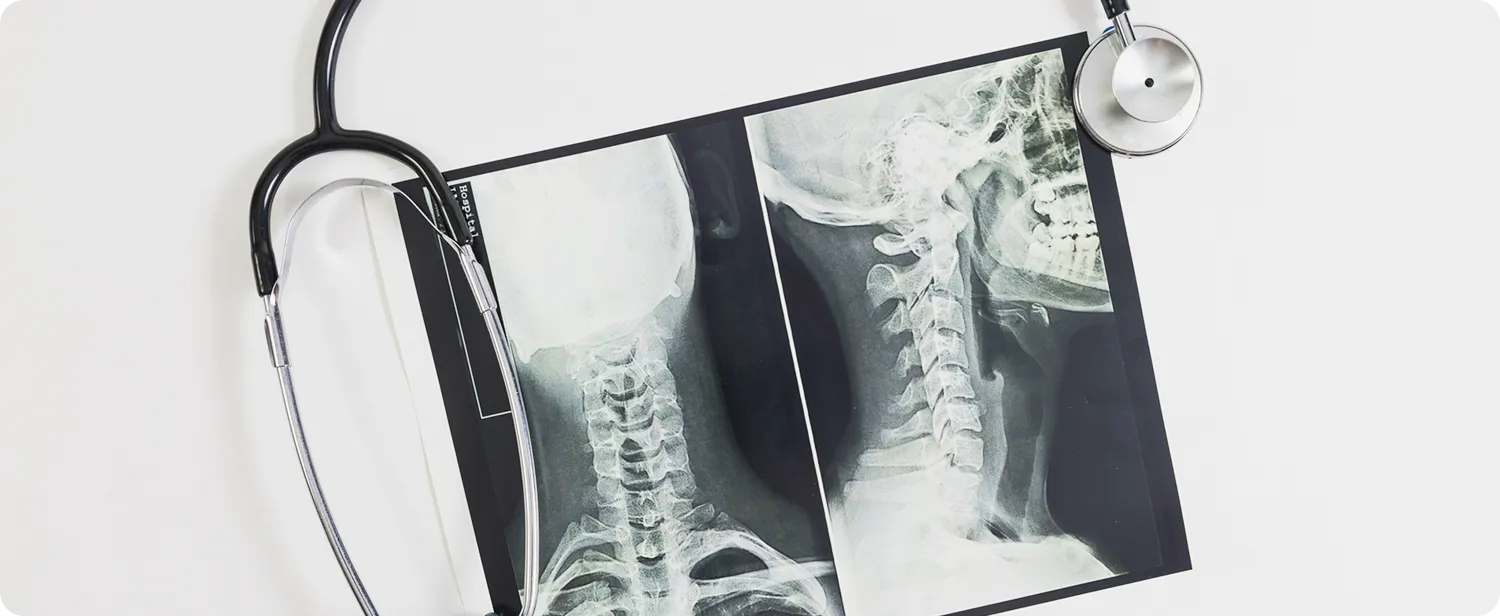

Современные цифровые рентген-аппараты позволяют получать чёткие снимки с минимальной лучевой нагрузкой. Быстро, точно и безопасно для вашего здоровья.

Технологии последнего поколения обеспечивают высокую точность и чёткость изображений, что помогает врачам быстрее и эффективнее ставить диагнозы. Этот метод используется для диагностики широкого спектра заболеваний, включая заболевания костей, суставов, органов грудной клетки и других частей тела.

Рентгенография — это быстрый и информативный метод диагностики, который позволяет оценить состояние костей, суставов, легких и других органов. В нашем центре установлено современное цифровое оборудование, которое обеспечивает высокую точность снимков при минимальной лучевой нагрузке.

Рентгенография — это не просто «фотография» изнутри. Это мощный диагностический инструмент, который позволяет врачу увидеть то, что скрыто от глаз, и поставить точный диагноз за считанные минуты.

Этот метод остается «золотым стандартом» в медицине благодаря своей непревзойденной достоверности. Он не только выявляет проблему, но и становится надежным помощником врача в отслеживании динамики лечения: будь то срастание перелома, рассасывание воспаления в легких или правильность установки импланта.

- Неврология и вертебрология: диагностика грыж межпозвонковых дисков, протрузий, искривлений позвоночника.